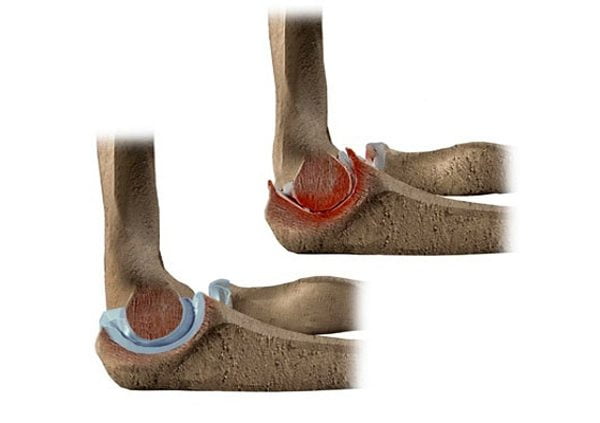

Патологические изменения развиваются вследствие функциональной перегрузки сустава: в нем возникает нарушение кровообращения и ухудшение питания хрящевой ткани. Из-за происходящих изменений она истончается и деформируется. Хрящ перестает быть эластичным, появляются трещины, суставные поверхности приобретают «шероховатые» очертания. При движении и нагрузке на сустав ощущается дискомфорт и боль в локте, которая со временем приобретает интенсивный характер.

Периодически сустав может «заклинивать»: возникает «блокадная» резкая боль с одновременным его обездвиживанием. Это явление обусловлено ущемлением участка измененного некротизированного хряща между суставными поверхностями и называется «суставной мышью». При последующих движениях эта блокада снимается, параллельно уменьшается боль, а сустав обретает подвижность.